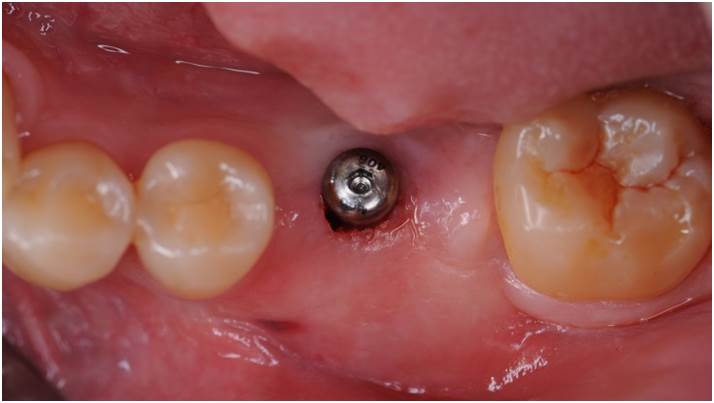

Clinical case: Bone filling into the bottom of deepest thread at 8.0mm AnyRidge fixture

- Courtesy of Dr. Kwang Bum Park -

Keywords

AnyRidge, Knifethread ,extraction socket, ,initial stability ,Allograft, ,osseointegratio ,Dr. Kwang Bum Park, , Mandibular, Single replacement, AnyRidge, Mega-oss,

Products used

Implant system-AnyRidge, Regeneration-Mega-Oss